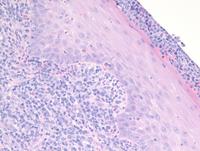

CD10-Positive Blastoid Variant of Mantle Cell Lymphoma

Category: Lymphoma: Mature B-cell and Plasma cell Neoplasms > Mantle cell Lymphoma > Blastoid variant

The expression of CD10 is typically missing in MCL. Only about 5% of cases express CD10. However, this becomes much more frequent in cases with Blastoid morphology, an aggressive form of MCL in which cells mimic lymphoblasts with larger size and a dispersed chromatin pattern.